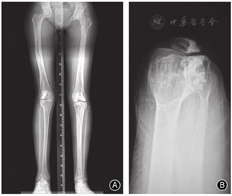

女,6岁,因右膝严重外翻畸形入院。4年前下楼扭伤膝关节,其后逐渐出现外翻畸形并跛行。体格检查:右膝关节外翻约28°,伸-30°、屈130°,挛缩的髂胫束制约膝关节伸直,髌骨固着在外侧,小腿相对大腿于外旋位(图1)。Kujala髌股关节功能评分49分。影像学检查:右膝关节X线片示胫骨后外旋转移位,内侧胫骨平台凸起,髌骨向外侧脱位,股胫角155°,股骨髓内可见致密的条状纹理(图2)。

术后4个月,因胫骨内翻畸形行近端骨骺外侧阻滞术,6个月后获得矫正(图4)。术后10个月,因下肢内旋和股骨超长2 cm,行股骨下端外旋短缩截骨术,3个月后截骨愈合。

术后19年复查,下肢发育基本对称,膝关节伸屈0°-140°,无不适症状,能参加体育活动。X线片示胫骨平台平整对称,股胫角170°,髌股关节正常,骨硬化无进展(图5)。Kujala髌股关节功能评分98分,Tegner评级4级。生育一女,发育正常。